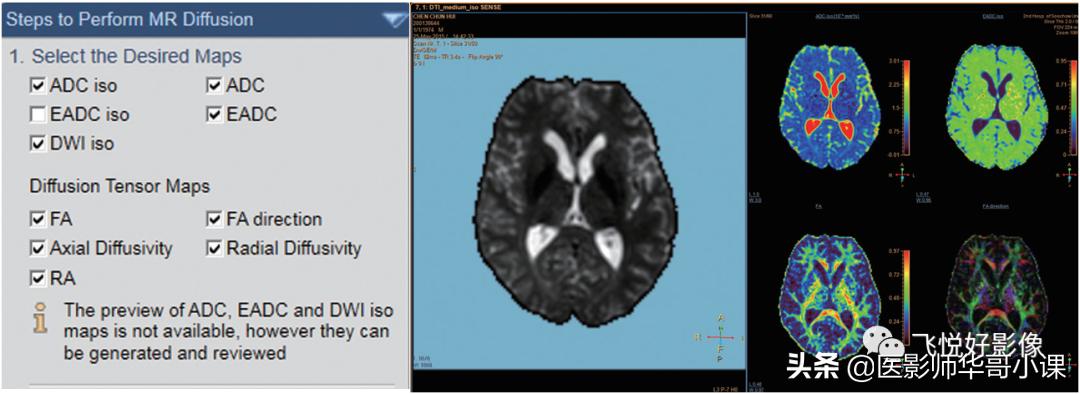

选择需要的视图:在图8左侧栏中选择需要视图,并打勾,DTI序列可选择FA相关视图。

图8.选择视图

选择视图后,继续进行第二步操作,对图像背景噪声进行遮噪(图9箭头所示)。遮噪时注意不能过度遮噪,掩盖扫描的组织图像。

图9.选择遮噪

上述步骤完成后,可保存新的Map序列,包括ADC图、FA图等。

图10.生成新图像